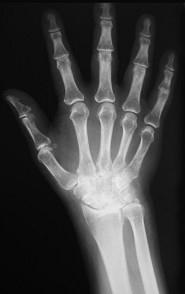

类风湿手X线(如图)的特点是 ( )A、软组织肿胀,关节变形B、关节游离体C、骨质硬化及增生D、骨质疏松E、关节间隙狭窄

问题 类风湿手X线(如图)的特点是 ( )

选项 A、软组织肿胀,关节变形 B、关节游离体 C、骨质硬化及增生 D、骨质疏松 E、关节间隙狭窄

答案 ADE